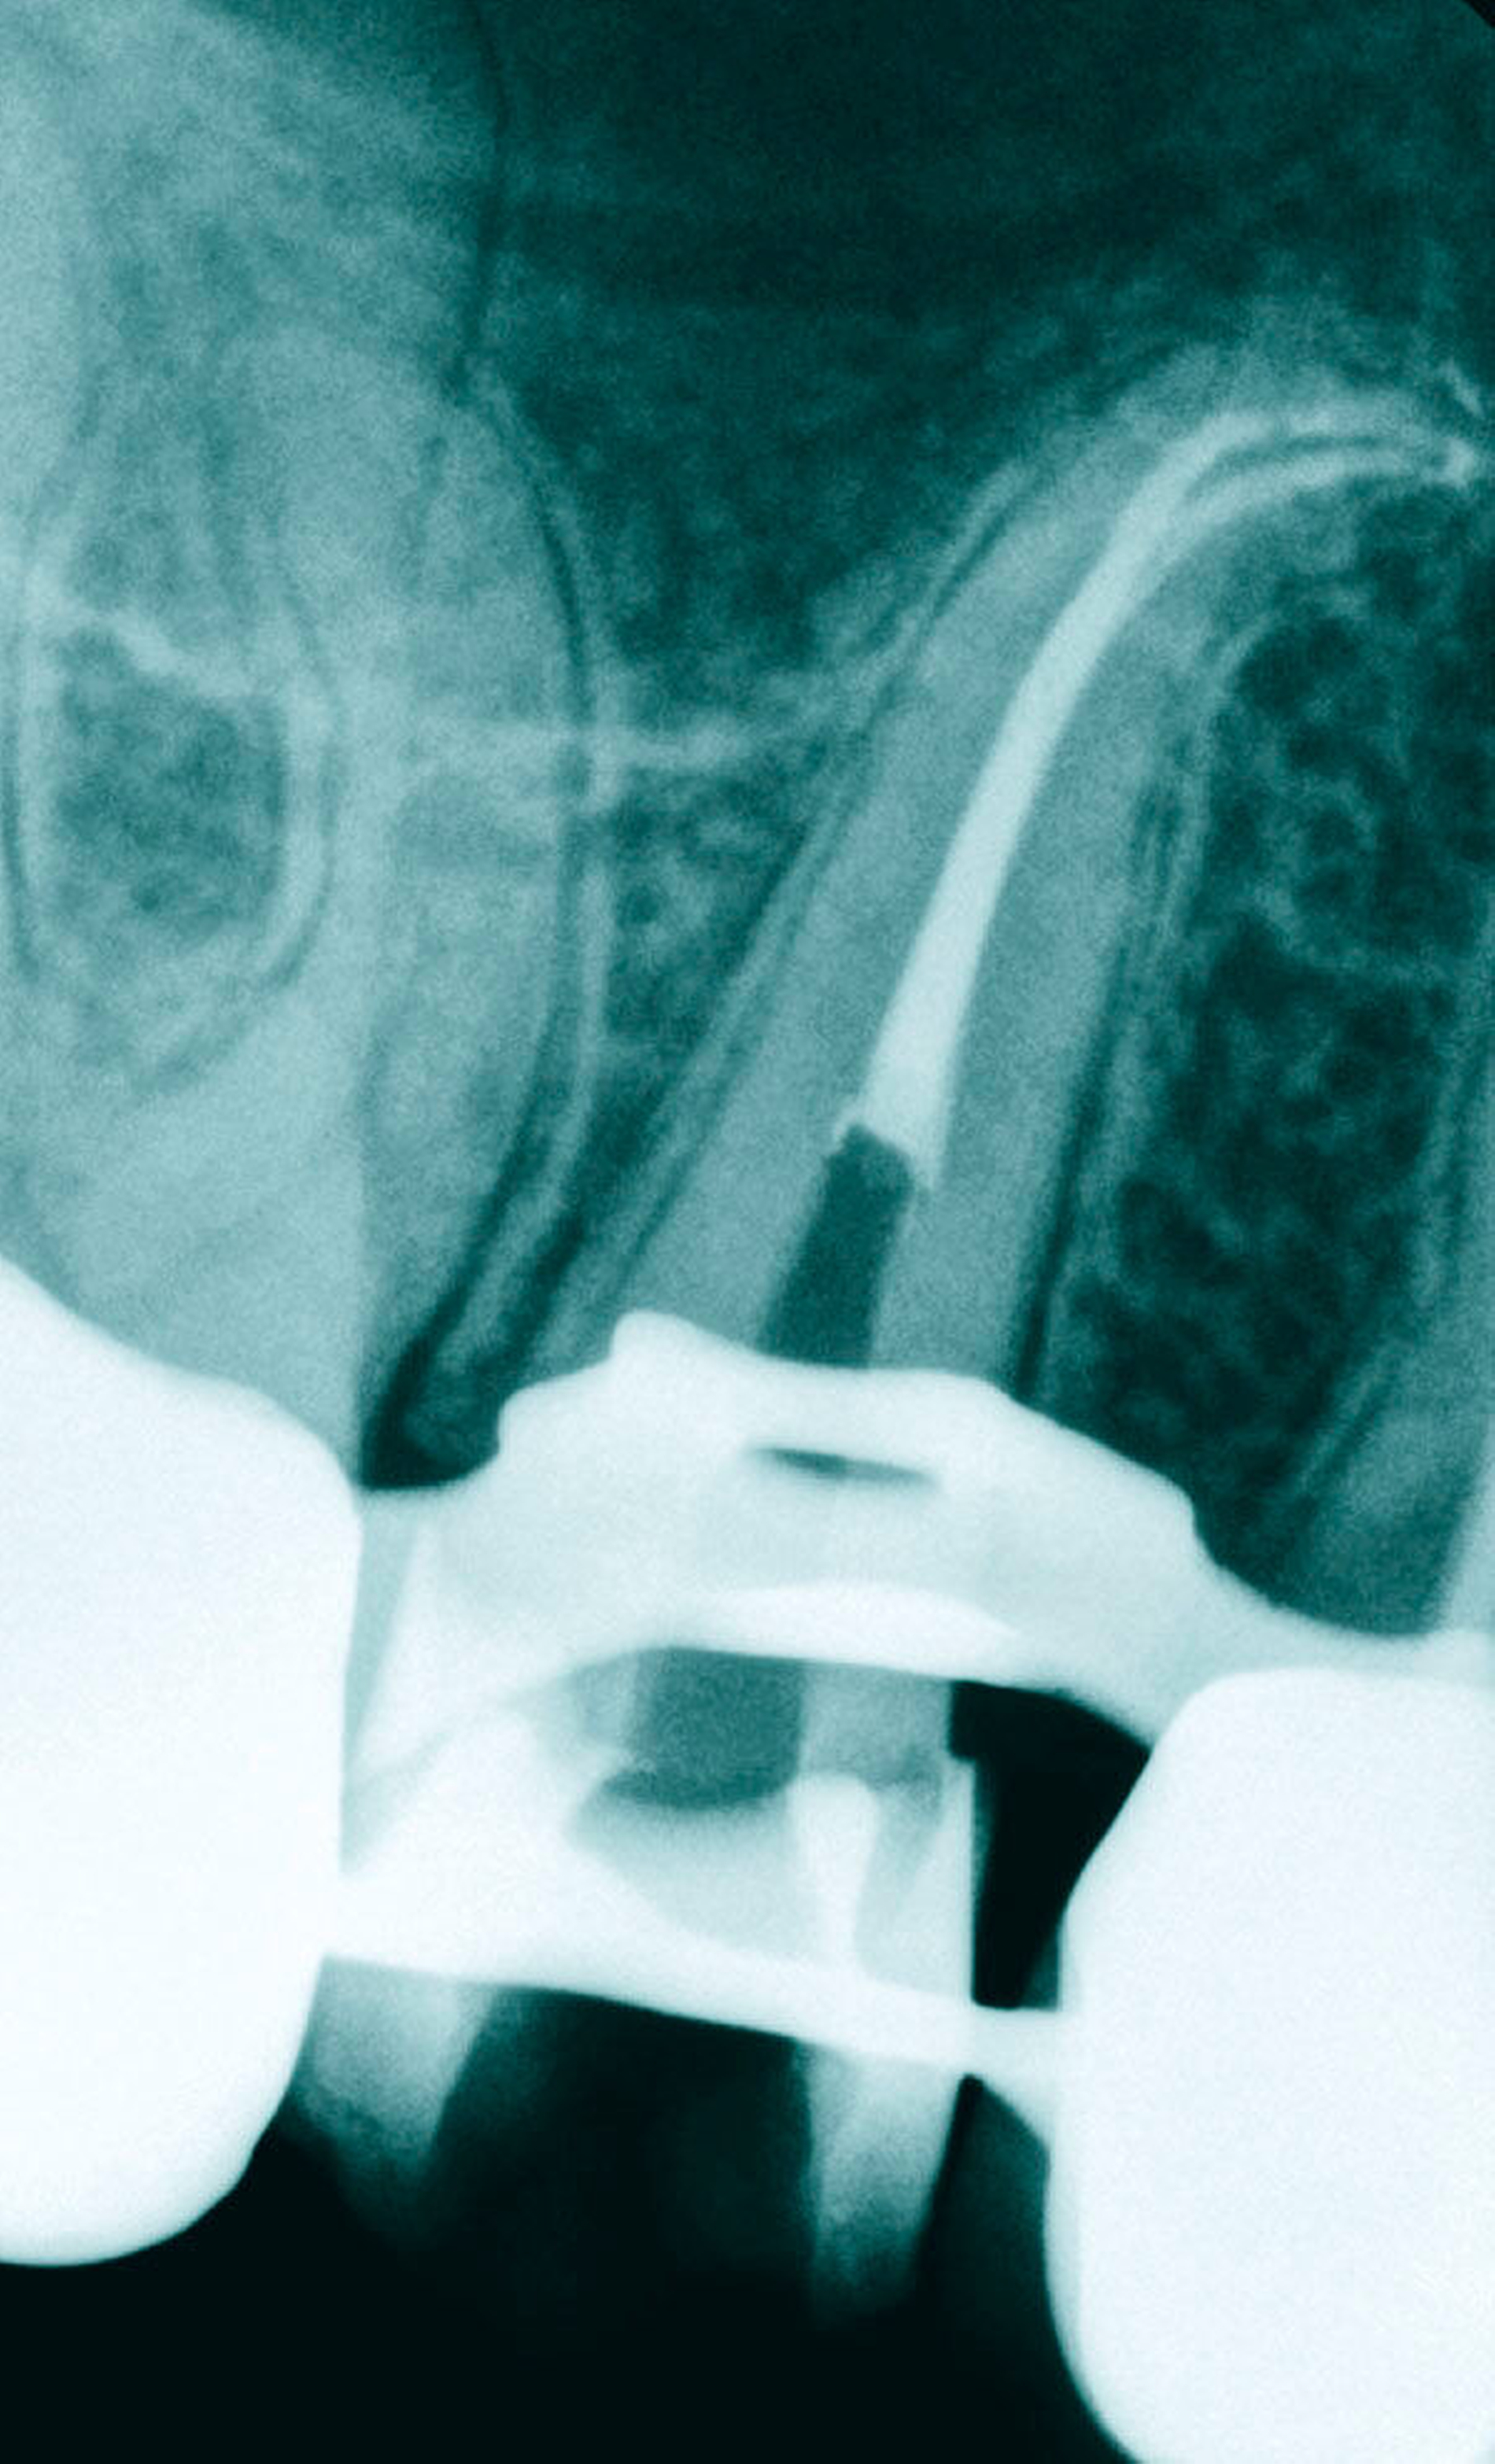

Bestehen großflächige Restaurationen, Kronen oder Brücken, kann das Auffinden der beiden Kanäle sehr schwierig sein. Allgemein konnte gezeigt werden, dass bei restaurierten Zähnen im Vergleich mit einem entsprechenden kontralateralen, restaurationsfreien Zahn eine erhebliche Einengung der Wurzelkanäle stattgefunden hat [Fleig et al., 2017]. Dies kann bei den ohnehin schon eher kleinen Kanälen oberer Prämolaren zu einer erheblichen Einengung und daher zu Schwierigkeiten beim Auffinden dieser Kanäle führen (Abbildung 4).